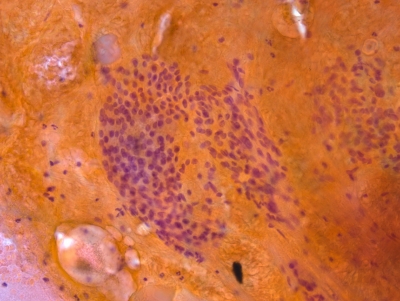

Home > ATYPIA OF UNDETERMINED SIGNIFICANCE or FOLLICULAR LESION OF UNDETERMINED SIGNIFICANCE > Atypia of Undetermined Significance (AUS)

Representative of sample showing aggregates of degenerate follicular cells in a bloody sample. Probably benign, but the cellularity and nuclear overlap caused insecurity in the observer's opinion. Thus AUS.

Keywords: Atypia of Undetermined Significance